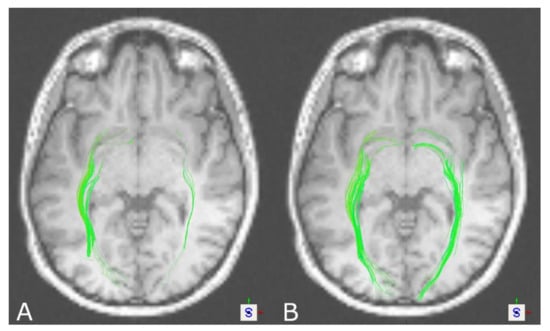

3.1. The Corticospinal Tract

3.2. The Optic Radiation